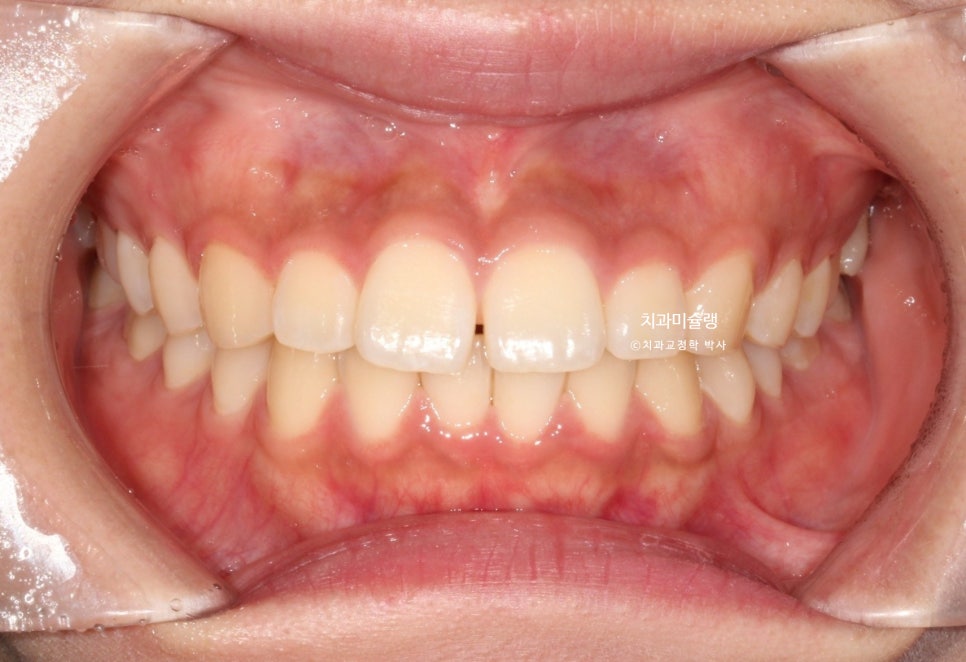

작년 겨울, 앞니 벌어짐과 약간의 돌출감 때문에 오신 환자분입니다.

중심선 불일치, 앞니 벌어짐이 보입니다.

위 앞니가 뻗쳐있고 튀어나와있네요.

작은어금니를 발치할 정도의 돌출은 아니라 비발치 돌출입 교정 권유드렸습니다.